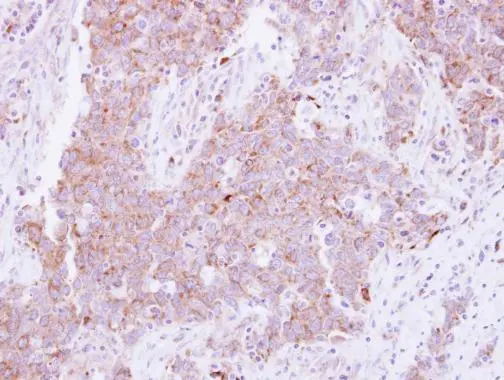

Anti-CD81 antibody used in IHC (Paraffin sections) (IHC-P). GTX101766

Immunohistochemical analysis of paraffin-embedded human lung Papillary adenocarcinoma, using CD81(GTX101766) antibody at 1:250 dilution.

Antigen Retrieval: Trilogy™ (EDTA based, pH 8.0) buffer, 15min